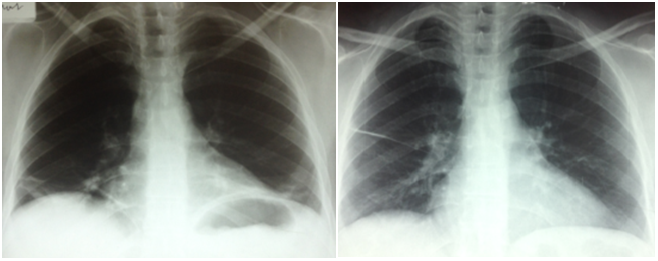

In addition to controlling any inflammation pulmonary rehabilitation may be helpful in maximizing lung capacity and training the body to use accessory muscles those that are not used for normal. Progressive dyspnoea with gradual elevation of hemidiaphragms on serial chest X rays are characteristic. We report on a patient with systemic lupus erythematosus who developed a shrinking lung syndrome.